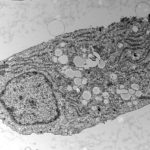

(SARS-CoV-2-Immagine Credit Scitechdaily).